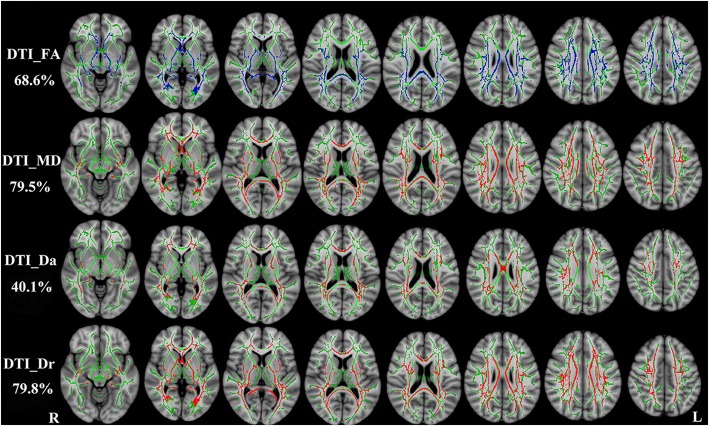

Diffusion parameters from DTI

RRMS patients exhibited similar patterns with DKI-derived diffusion parameters. FA was reduced, MD, Da and Dr were increased (P < 0.01, two-tailed, FWE corrected). DTI_FA, DTI_MD, DTI_Da and DTI_Dr could detect abnormal diffusion in 68.6%, 79.5%, 40.1% and 79.8% voxels of the whole WM skeleton respectively. DTI-derived diffusion parameters are shown in Fig. 3.

Fig. 3.

TBSS shows WM regions with significant differences in the DTI_FA, DTI_MD, DTI_Da and DTI_Dr between RRMS patients and healthy subjects (P < 0.01, FWE corrected). Green represents mean FA skeleton of all participants; red denotes increase and blue represents reduction in RRMS patients. The percentage in the left column represents the percentage of the abnormal voxels relative to the whole skeleton voxels for each parameter